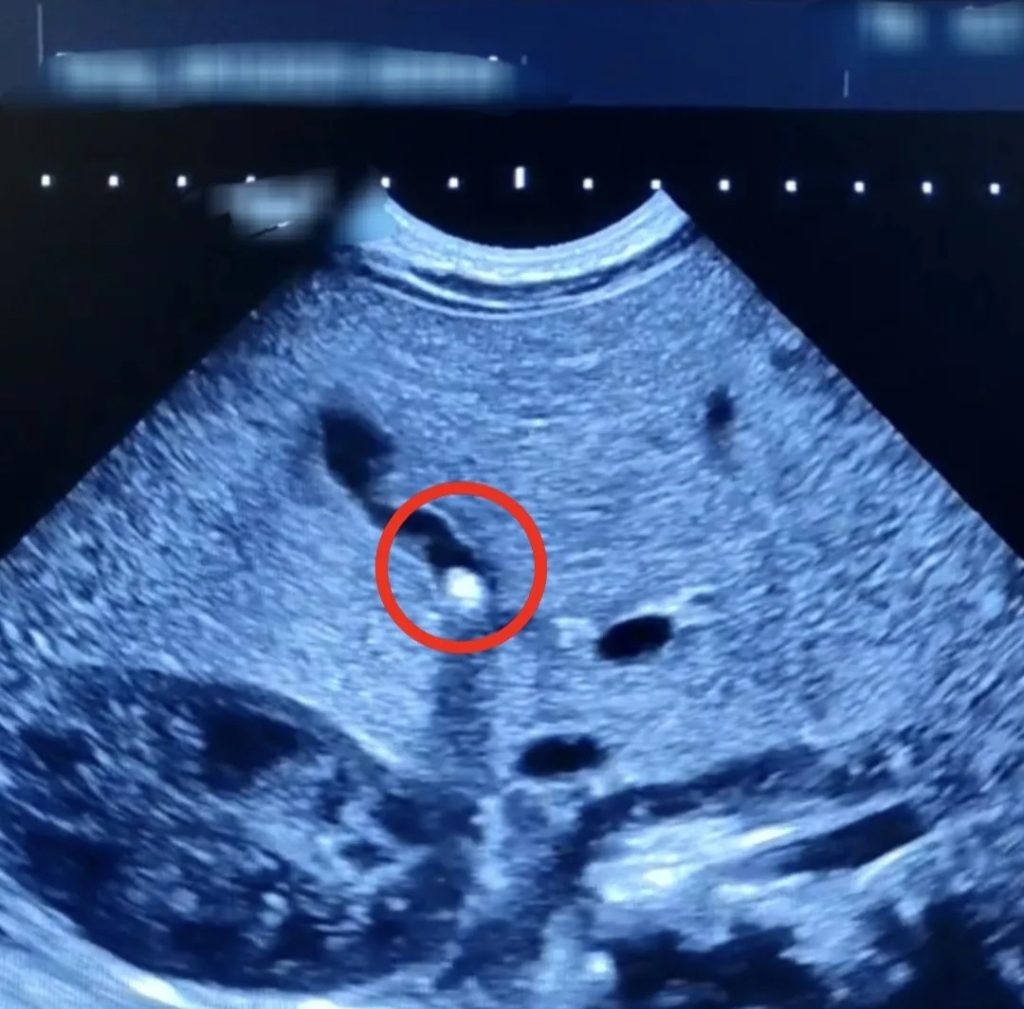

Редкий случай: в Балаковской городской клинической больнице у 1,5-месячного малыша медики выявили камень в жёлчном пузыре

“В декабре текущего года эта патология, характерная для взрослых, была диагностирована у полуторамесячного младенца. При проведении УЗИ брюшной полости у него был обнаружен камушек в желчном пузыре.

В стационар БГКБ обратилась мама младенца с жалобами на плохую прибавку массы тела и желтушное окрашивание кожи и склер у малыша. Обследовав маленького пациента, врачи выяснили, что желчный проток у него частично закрыт камнем небольших размеров. Медики начали необходимое лечение. Им удалось не только улучшить отток желчи из желчного пузыря ребенка, но и добиться стабильной прибавки в весе, которой не наблюдалось в первый месяц его жизни. Сейчас малыш выписан домой и находится на амбулаторном наблюдении.